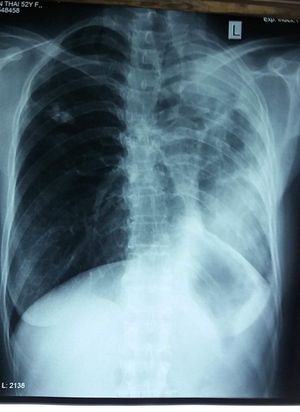

Man 55 years old come with Severe dyspnea associated with severe oxygen desaturation: SpO2 87-89%. Does not have a fever. Any ideas please?

Hyperlucency of the right lung with trachea deviated to the left

Mediastinal shiftΒ is towards the affected side so it can be left atelectasis or left lung collapse

Left atelectasias , plus right massive pneumothorax

Is there bowel in the thoracic cavity?

Diaphragmatic hernia? Just a layman girl with a medical interest.